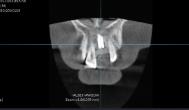

检查: 1. 口腔检查 全口咬合关系基本正常。21缺失,缺失区牙槽骨丰满度欠佳,牙龈状况一般,为厚龈生物型,全口牙龈普通退缩约1-2mm,临床牙冠偏长,牙龈乳头缺损;缺牙区邻牙未见明显倾斜,缺牙颊舌向宽度约5mm。患者为轻度氟斑牙,牙冠颈部为B4色,体部基底色为A3色,颈1/3与牙冠体部分界明显。其主要特征为牙面可见少量白垩色条纹。牙石及色素(++),牙齿轻度磨耗;开口型正常,开口度约三横指,笑线低。 2. 术前影像学检查 CBCT显示:21牙缺失。骨质III类。近、远中牙槽间隔顶至邻接点距离为6mm。牙槽嵴距离鼻底为20.43mm。缺失牙牙槽嵴宽度约4mm。